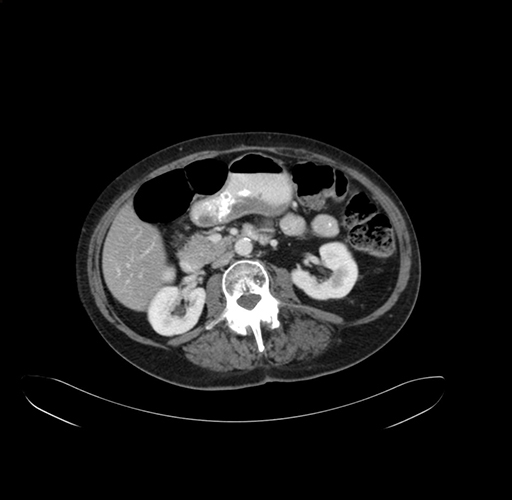

Pre-Chemo: Axial Venous